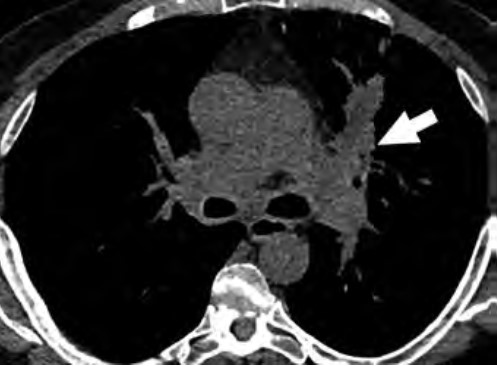

At the individual level, some of the barriers to awareness include unfamiliarity with LCS as a health preventive service tool (Fig. 2), unawareness of the new USPSTF and Centers for Medicare & Medicaid Services (CMS) recommendations for LCS, unfamiliarity with insurance coverage and costs, uncertainty about available accredited LCS programs, lack of culturally appropriate information, and lack of information at an appropriate health literacy level [8–10].